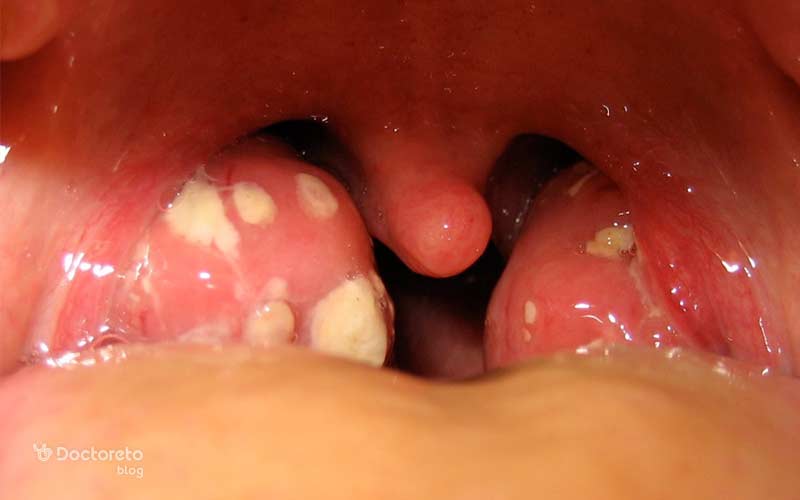

عکس لوزه چرکی

لوزه چرکی یا آبسه دور لوزهای معمولاً نتیجه التهاب حاد لوزه است که بهدرستی درمان یا کنترل نشده باشد. در این حالت، چرک در اطراف یا بین لوزهها تجمع پیدا میکند و ظاهر سفید یا زرد رنگ مشخصی ایجاد میشود. این وضعیت اغلب با درد شدید گلو همراه بوده و باعث احساس گیر کردن چیزی در گلو میشود.

از علائم شایع لوزه چرکی میتوان به درد شدید هنگام بلع، دردی که به گوش انتشار پیدا میکند، افزایش ترشح بزاق و مشکل در باز کردن کامل دهان اشاره کرد که باید سریعا به پزشک مراجعه کرد. تب نیز یکی از نشانههای رایج این نوع التهاب است و معمولاً نشاندهنده شدت عفونت است.